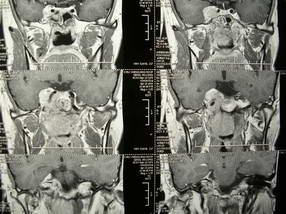

男、30、发现鼻咽部肿瘤侵犯海绵窦,未发现明显淋巴肿。请问国内那家医院治疗鼻咽部肿瘤最好?手术以何种方式为主?病灶可否全部切除?急切期待的大家的帮助。

扫描示鼻咽腔不对称,中度狭窄,右侧咽隐窝消失,局部软组织肿块,鼻咽右侧壁增厚形成肿块,突入鼻咽腔,肿块平扫呈等密度,肿块向深部侵润,右侧翼内外肌受侵,右侧咽旁间隙变窄;向后生长,头长肌界线欠清,向后上生长侵犯同侧颈动脉鞘区。双侧海绵窦增宽,内见软组织影与鼻咽部肿块相连。考虑鼻咽癌。鼻咽癌主要是放射治疗,且效果较好;到当地有治疗设备较大医院治疗即可。

这个病例有点特殊,和常见的鼻咽癌不太一样,以向颅内侵犯为主,骨质破坏区小。鼻咽癌首先要考虑,有没有其他可能?本人不会看mr片,期待有人能讲解,期待病理。

鼻咽部新生物侵犯右侧中颅窝底及右侧海绵窦,鼻咽癌可能性大。建议增强扫描。纤维血管瘤禁忌穿刺。